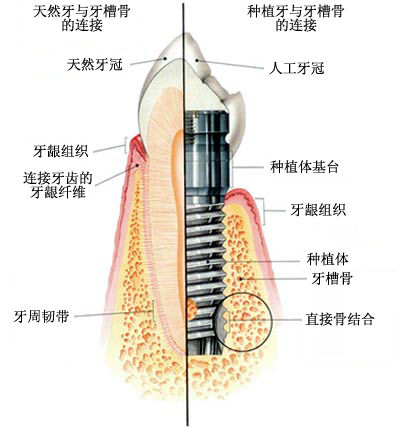

ЁЁЁЁЖдгкжжжВбРЃЌЯраХДѓВПЗжШЫЖМЬ§ЫЕЙ§ЃЌЕЋЪЧИїЮЛгжЪЧЗёгаЩюШыСЫНтЙ§ФиЃЌЯТУцОЭЮЊДѓМвМђЕЅЕиПЦЦевЛЯТЪВУДЪЧбРГнжжжВЁЃ

ЁЁЁЁЫљЮНЕФжжжВбРЃЌОЭЪЧжИдкбРВлЙЧФкжВШыЩњЮяВФСЯжЦГЩЕФШЫЙЄбРИљЁЂгУвджЇГжКЭЙЬЖЈбРЙкЕФШБбРаоИДЗНЪНЃЌЦфЙІФмгыЭтЙлМИКѕгыецбРвЛбљЃЌБЛГЦЮЊШЫРрЕФ“ЕкШ§ИБбРГн”ЁЃ

ЁЁЁЁ1ЁЂЪжЪѕЧАвЊЯШзіИіПкЧЛШЋОАЦЌЃЌвдШЗБЃбРВлЙЧЪЪКЯзіжжжВбРЃЌжЎКѓдйгЩвНЩњЩшМЦГіОпЬхЕФжжжВЗНАИЁЃ

ЁЁЁЁ2ЁЂЪжЪѕПЊЪМЃЌЯШдкбРВлЙЧЩЯБИПзВЂжВШыжжжВЬх(ШЫЙЄбРИљ)ЃЌШЛКѓЕШД§3~6ИідТЕФЙЧНсКЯЦкЁЃ

ЁЁЁЁ3ЁЂАВзАгњКЯЛљЬЈЪЙжжжВЬхДЉГібРіИЃЌЕШД§2~3жмШУШэзщжЏГЩаЮЁЃ

ЁЁЁЁ4ЁЂШэзщжЏГЩаЮКѓгУгРОУЛљЬЈЛЛЯТгњКЯЛљЬЈЃЌНЯКѓАВзАЙЬЖЈжжжВбРЙкБуЭъГЩСЫжжжВбРЪжЪѕЁЃ